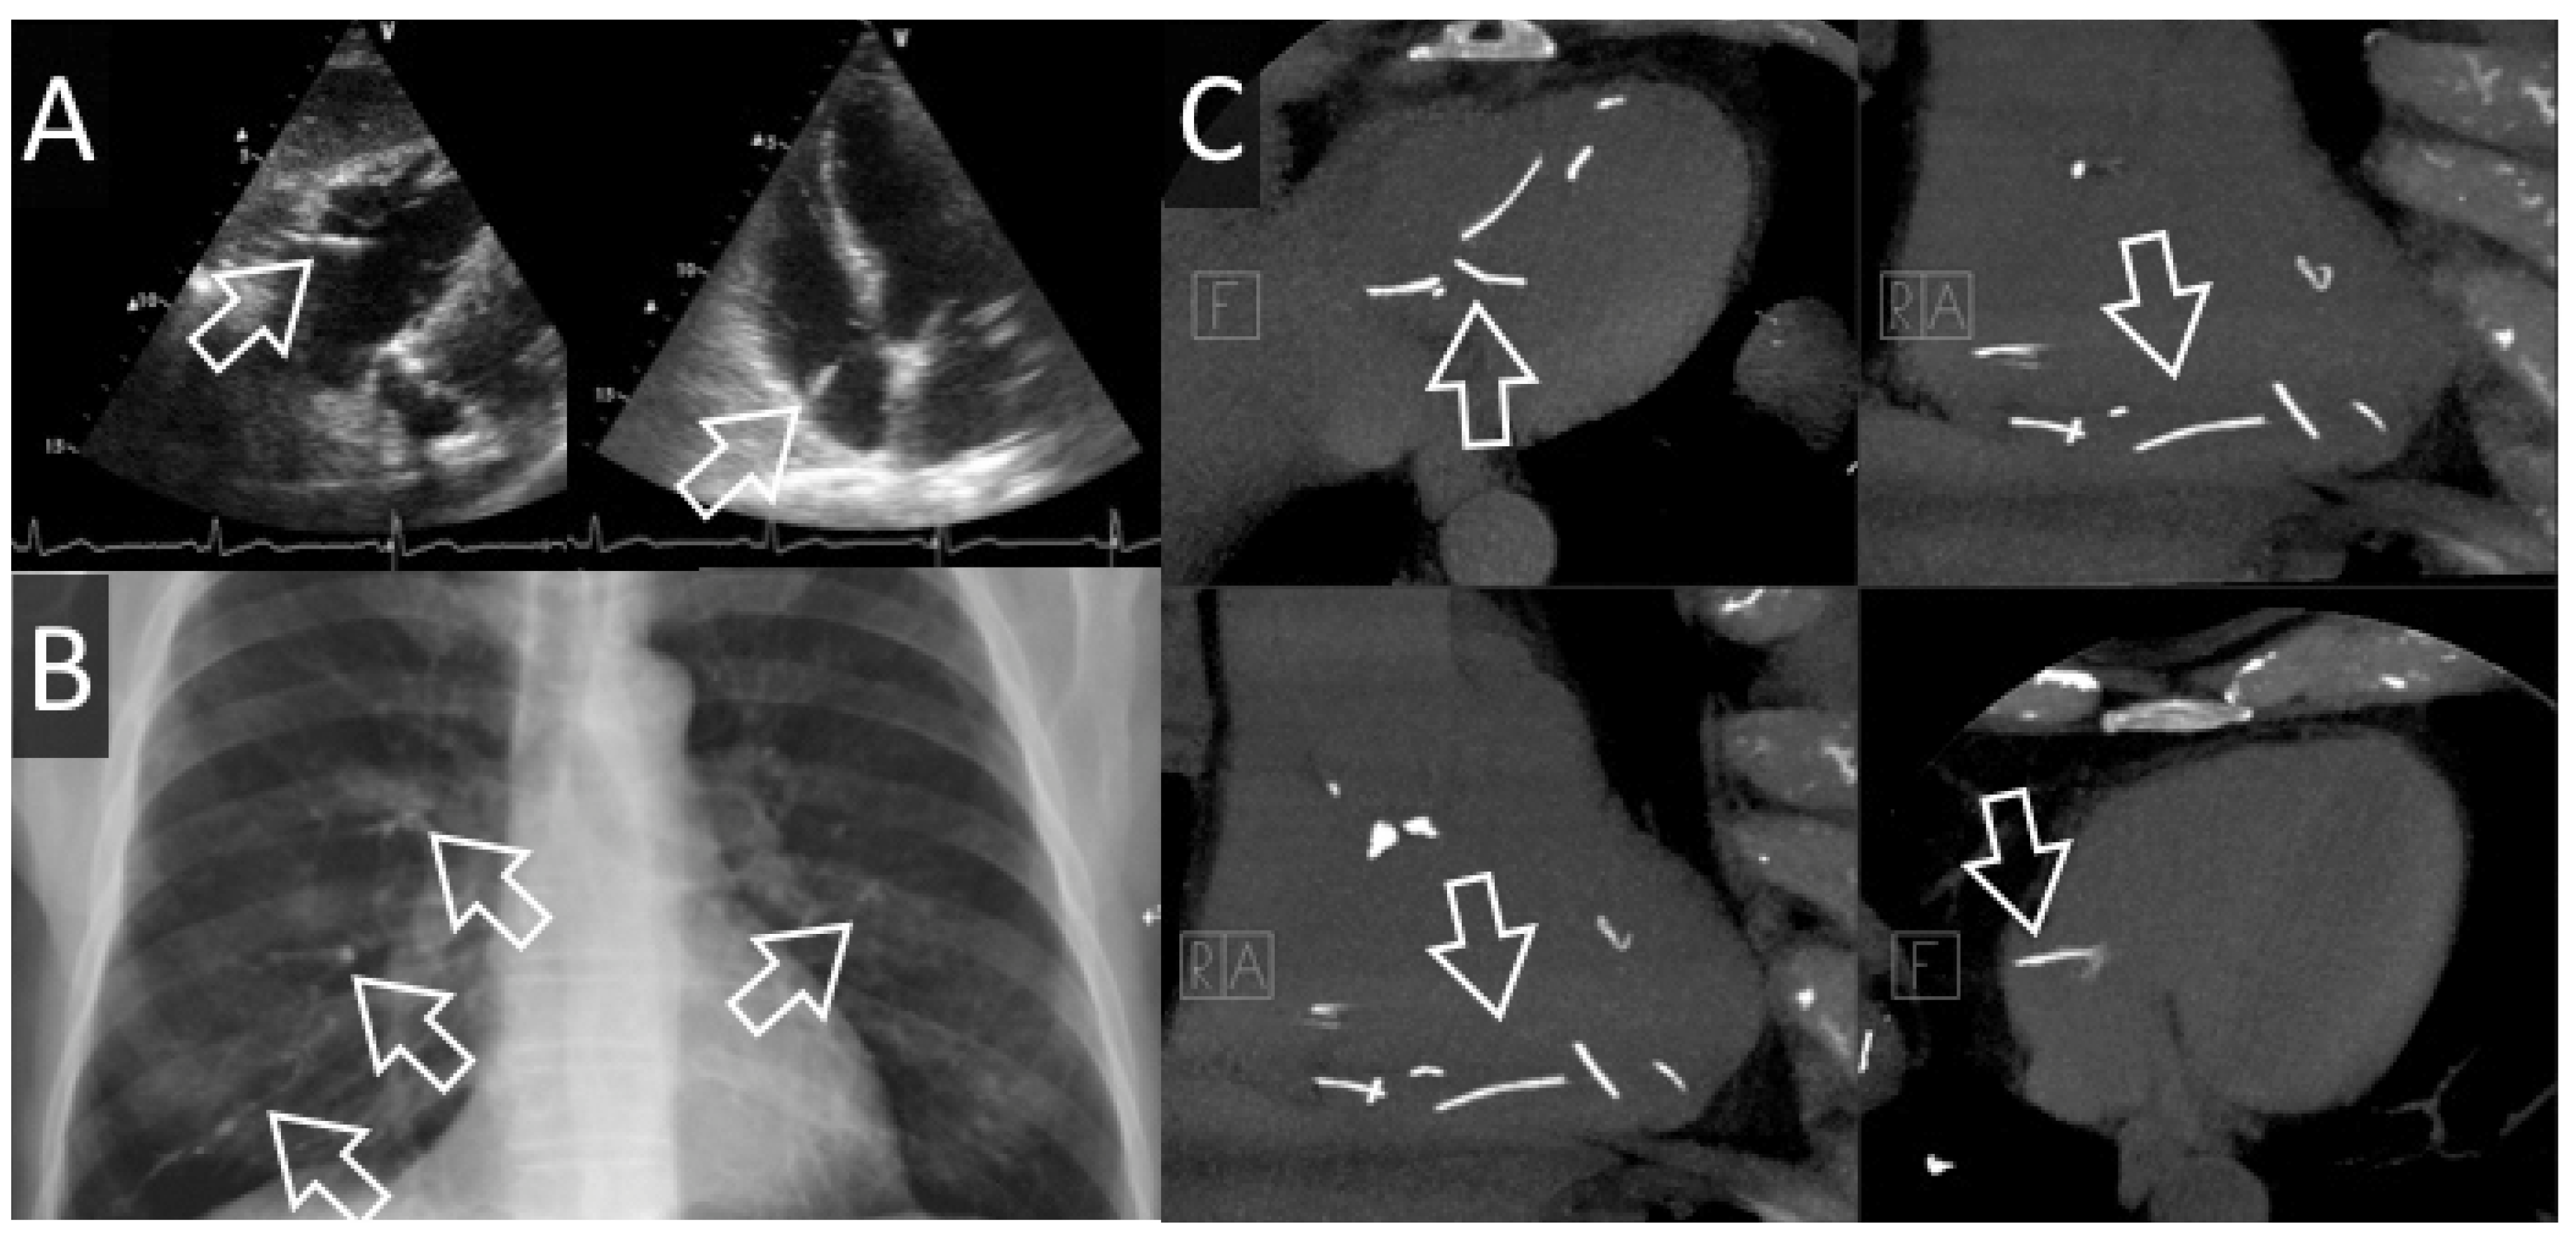

Figure 3. Cas #3. Panel A. Echocardiographie transthoracique révèle un filament de ciment (flèches blanches creuses) attaché à l’oreillette droite. Panel B. Des emboles périphériques sont visibles sur la radiographie de thorax. Panel C. Un CT thoracique confirme l’image échocardiographie (en bas à droite), mais révèle plusieurs autres fragments non clairement visualisés à l’échocardiographie.

Un patient de 72 ans, connu pour une maladie coronarienne monotronculaire (IVA moyenne), une sténose aortique modérée et un syndrome myélodysplasique, bénéficie de 2 vertébroplasties lombaires (L4, puis L3) dans le courant de l’été 2016. A l’issue de ces interventions, il développe une dyspnée stade NYHA IV mise sur le compte d’une embolisation pulmonaire de ciment qui sera confirmée par un angio-CT. Une échocardiographie exclut une hypertension artérielle pulmonaire et démontre une embolisation intracardiaque. Au vu de la taille des emboles et de l’absence d’hypertension artérielle pulmonaire, une attitude conservatrice est décidée et le bilan est complété par un CT-cardiaque. Ce dernier examen révèle la présence de multiples spicules millimétriques (5 au niveau duventricule droit et 1 au niveau de l’oreillette droite) et en périphérie des artères pulmonaires droites. Au vu de la taille et de la quantité de filaments chez un patient asymptomatique, l’attitude conservatrice est maintenue. Un suivi échocardiographique est effectué à 6 mois. L’évolution de la dyspnée est favorable, avec un stade NYHA II, 9 mois après l’embolisation.